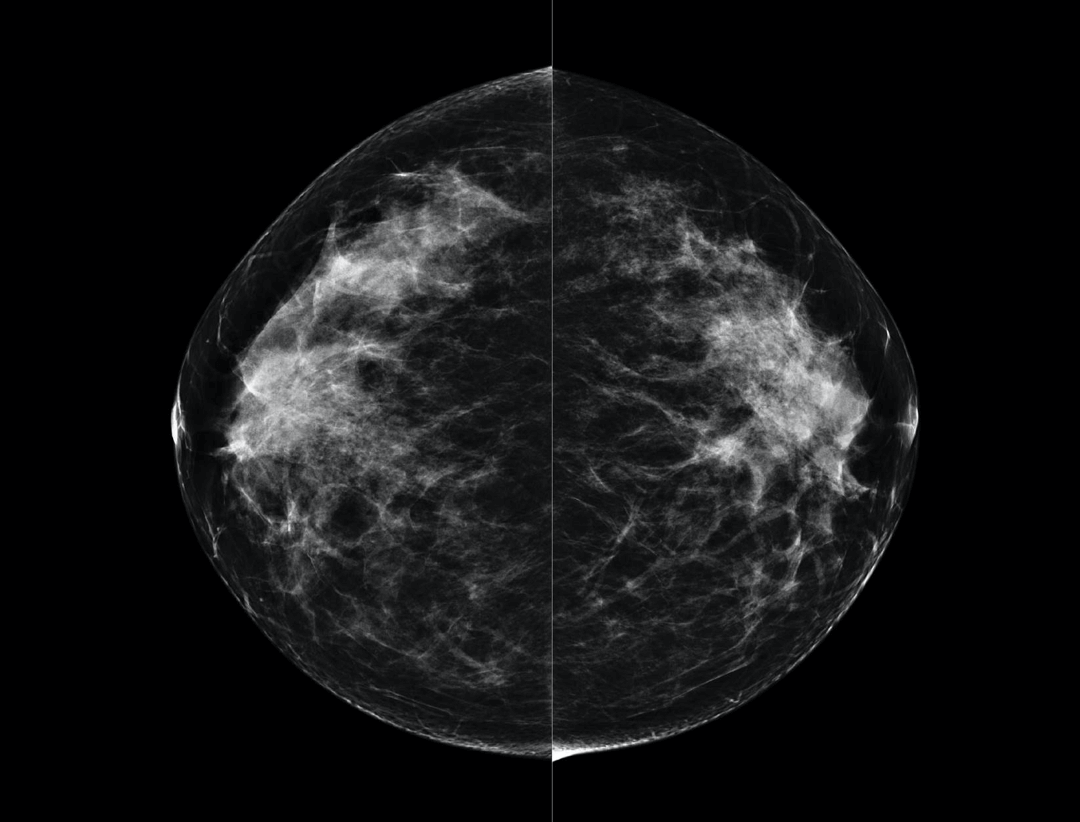

High Resolution Low Dose Imaging

Large coverage amorphous-silicon (a-Si) flat panel detector featuring an optimized active matrix array provides high spatial resolution and high image acquisition speed at a lower dose.

High performance tungsten target X-ray tube offers high resolution image for both dense and fatty breast densities.

Intelligntly detects breast density and thickness, then auto selects the appropriate filter combination.